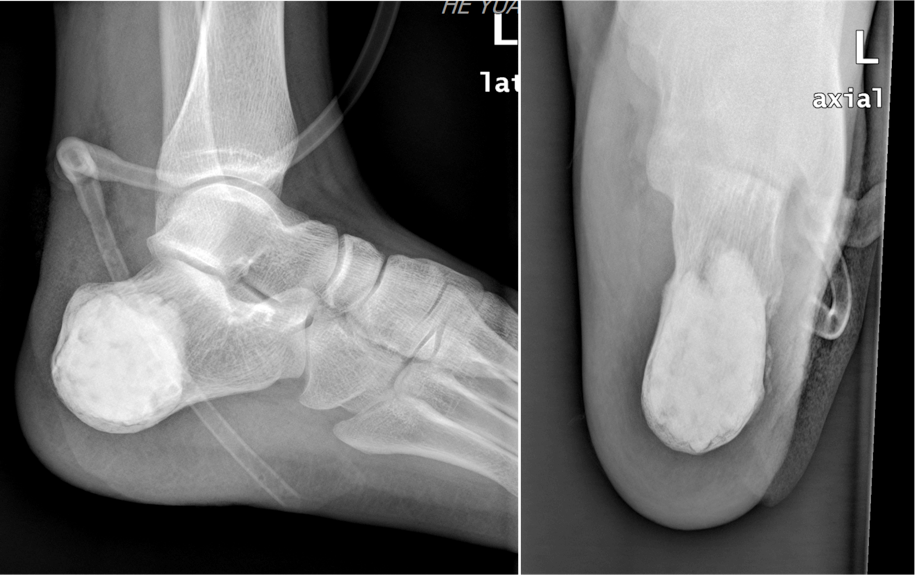

手术中,曾红生主任医师团队首先完整显露患者的左跟骨病灶范围,开窗后使用微波消融灭活瘤腔,进一步减少骨囊肿复发的可能性;其次,使用骨水泥+人工骨+骨修复材料复合体重建跟骨骨缺损。历经2小时,使患者重建了跟骨的解剖形态,使患者恢复了跟骨的承重与运动协调功能,足弓的正常形态和高度得以维持。术后病理证实为动脉瘤样骨囊肿。术后李先生积极进行功能锻炼,在医护工作人员的努力及李先生的配合下,最终康复出院。

▲骨水泥+人工骨复合体重建跟骨形态与功能